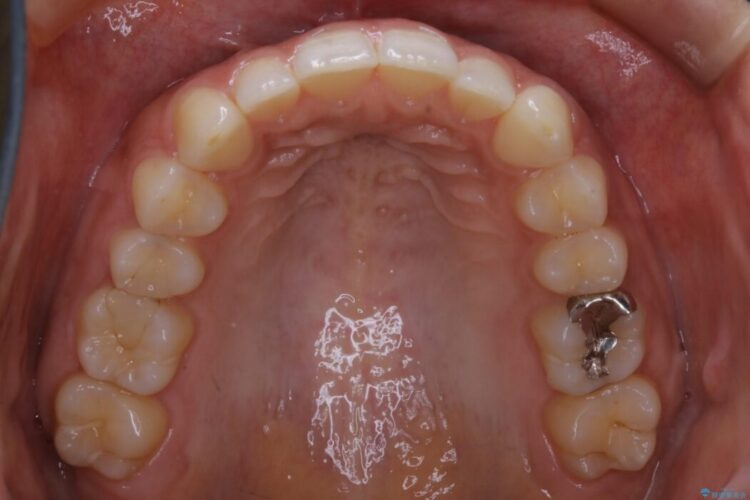

狭窄歯列について

狭窄歯列とは幅が狭くなっている歯並びのことです。

本症例では下顎の歯列が舌側へ傾くことにより幅が狭まっていましたので、マウスピース治療により歯列弓を拡大しました。